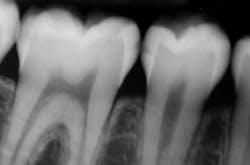

Question: According to the following image, the carious lesion on the distal of the premolar can be classified as:

- Incipient

- Moderate

- Advanced

- Severe

On the radiograph, the dark area protrudes more than half way through the enamel, but does not touch the DEJ. Therefore, this lesion is a moderate lesion. The lesion on the mesial surface of the molar on the other hand can be classified as incipient.